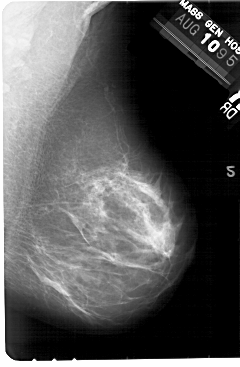

A_1445_1.RIGHT_MLO

RIGHT_MLO LINES 5491 PIXELS_PER_LINE 3586 BITS_PER_PIXEL 12 RESOLUTION 43.5 NON_OVERLAY